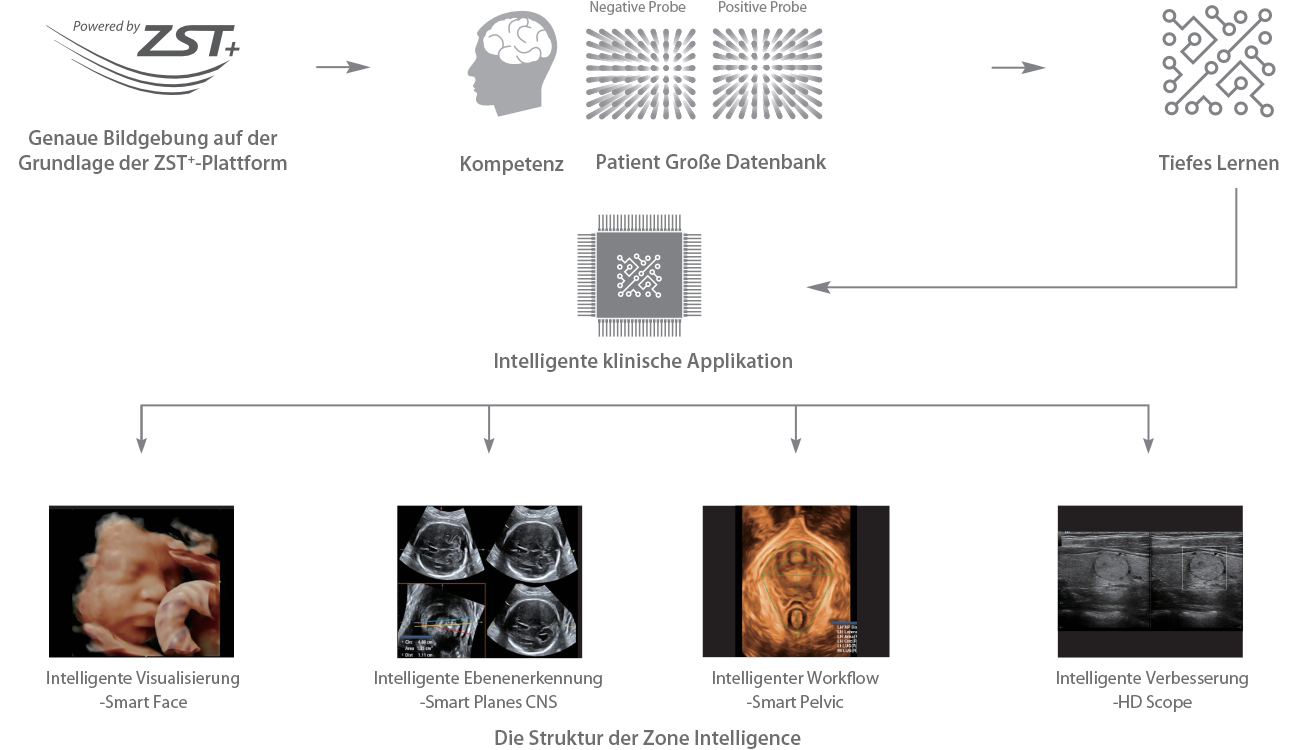

Seit der Gr├╝ndung des Unternehmens hat Mindray fortlaufend neue Wege zur Verbesserung der diagnostischen Zuverl?ssigkeit erforscht. Angetrieben von der revolution?rsten Technologie ZONE Sonography?, bringt die neue ZST+ Plattform von Resona 7 die Ultraschallbildqualit?t durch Zonenerfassung und Kanaldatenverarbeitung auf ein h?heres Niveau.

Neben der erstklassigen Bildqualit?t verbessert Resona 7 auch die klinischen Forschungsm?glichkeiten mit dem revolution?ren V Flow f├╝r die vaskul?re h?modynamische Bewertung und der intelligentesten Ebenenerfassung aus 3D-Datens?tzen f├╝r die f?tale ZNS-Diagnose. Mit der Kombination aus intuitiver, gestenbasierter Multi-Touch-Bedienung und allen wichtigen klinischen Funktionen ist das Resona 7 ein echter Wegbereiter f├╝r neue Ultraschall-Innovationen.